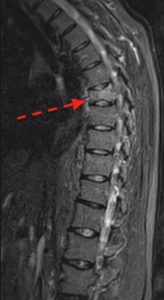

En fracturas agudas con colapso parcial de la vértebra, la cifoplastia (a diferencia de la vertebroplastia) puede restituir parte de la altura vertebral perdida para compensar el balance sagital.